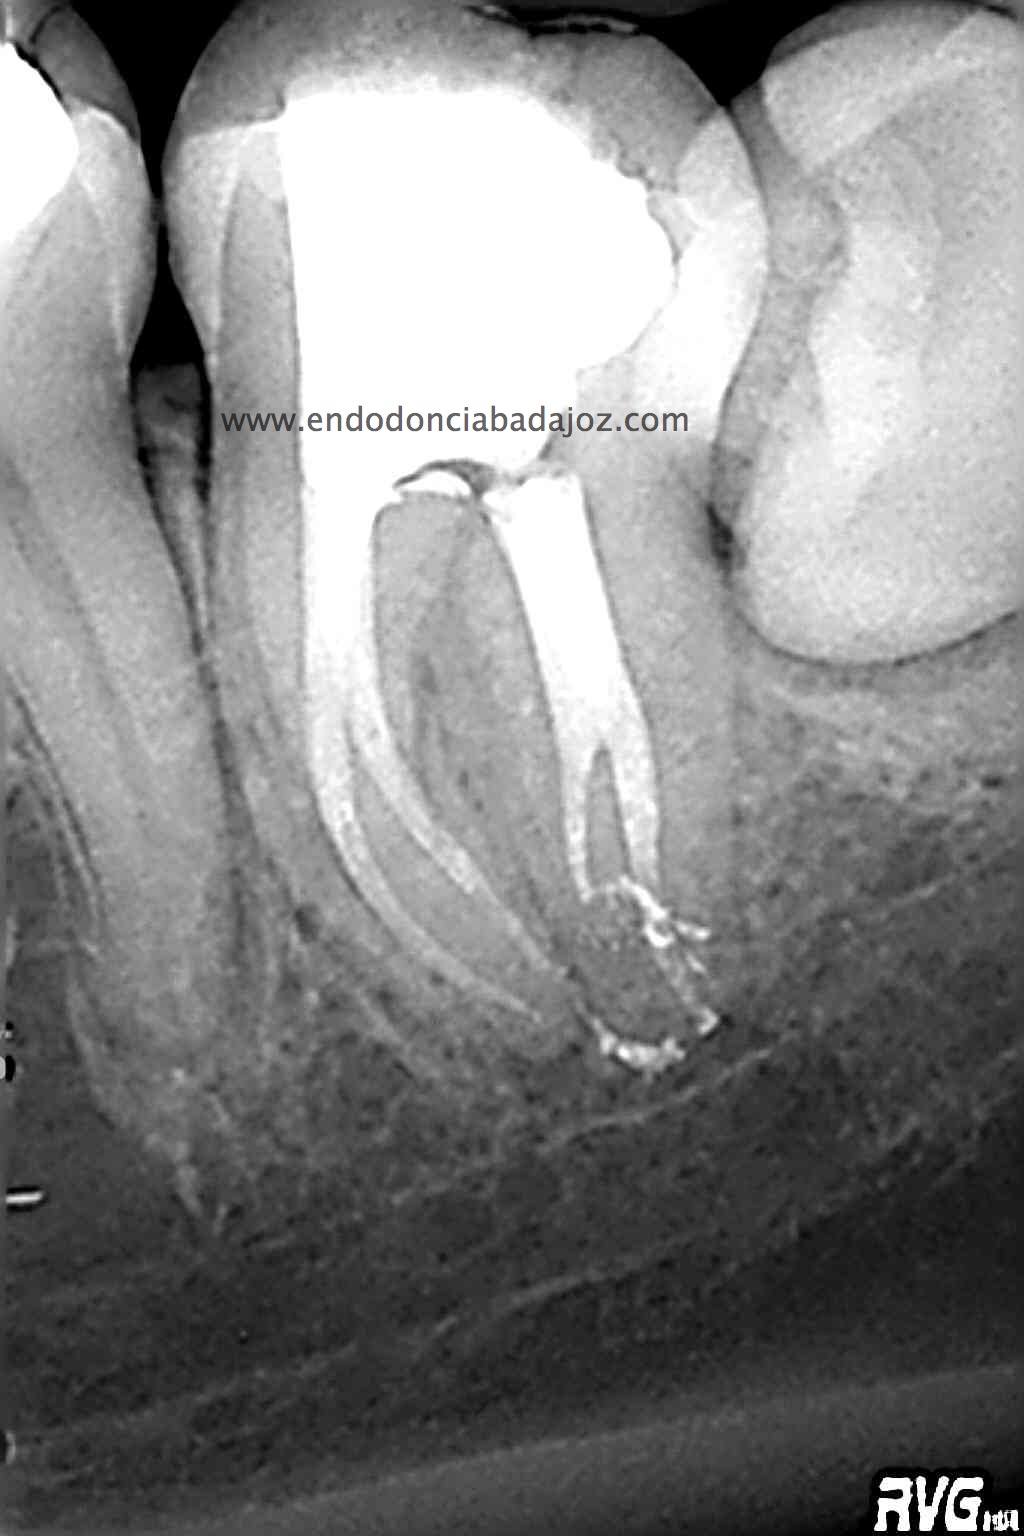

MOLAR INFERIOR CON 4 CONDUCTOS.

Se trata de un caso que ,a priori, traté como un 3.7 de tres conductos:

Después de haber instrumentado con un sistema Protaper, y habiendo estandarizado el conducto en un 25mm en apical y una conicidad del 6% con limas K3. observé que el conducto Distal presentaba otro conducto Disto-Vestibular cuya entrada estaba en la pared del conducto Disto-Lingual tratado, bastante complicado de trabajar.

Una vez que conseguimos un buen acceso, con ayuda de Microopeners y ultrasonidos, instrumentamos el conducto y finalmente obturamos todos con sistema de Ola Continua de Buchanan y un backfillin con gutapercha inyectada con Obtura II.